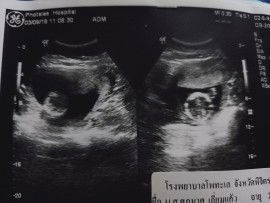

แม่ท้องได้ 15W อัลตร้าซาวด์แล้วออกมาแบบนี้ค่ะ ? ถือว่าปกติมั้ยค่ะ #ท้องแรกค่ะ แม่ต้องทำอย่างไงต่อค่ะ ขอความรู้จากแม่ๆหน่อยค่ะ #ขอบคุณค่ะ